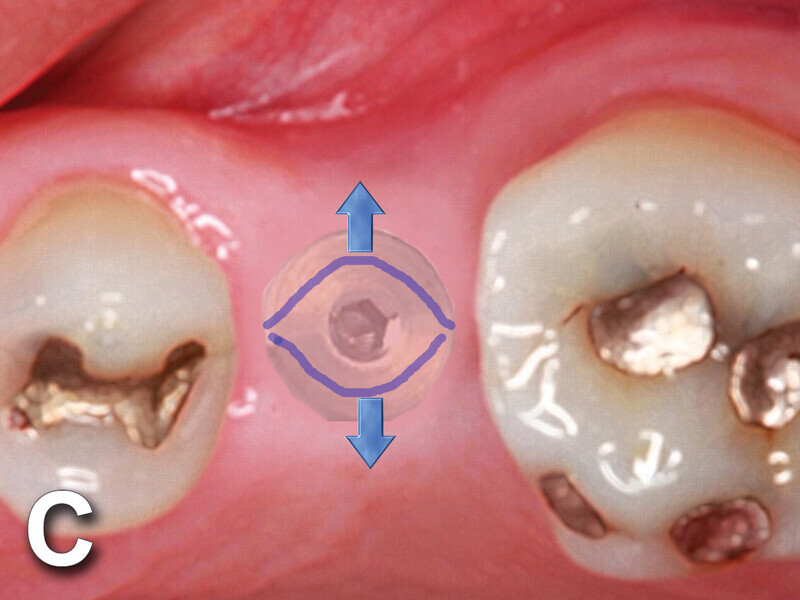

Fig. 4c: Implant to be uncovered (4a) presents with two options depending on width of attached gingiva available. Wide band of attached gingiva will remain after removal of tissue over cover screw, and the diode is utilized in a spiral pattern starting at center until fully exposed (4b). With the narrow band of attached gingiva present, an elliptical cut is made with the diode and tissue is pushed buccally and lingually to preserve the attached gingiva (4c). (Photo provided by Dr. Gregori M. Kurtzman)